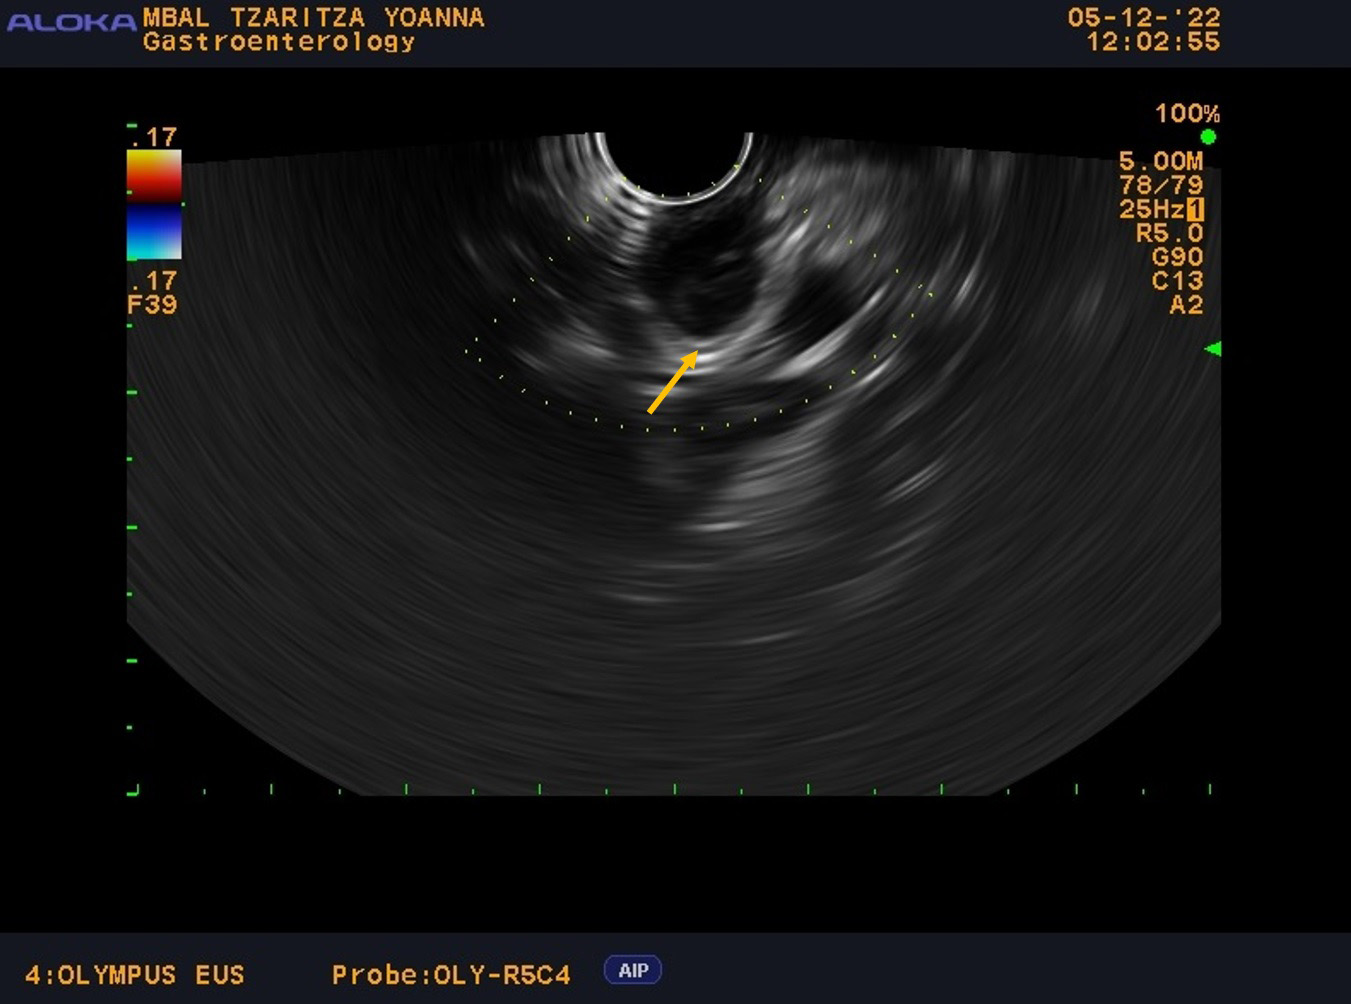

Throughout her hospital stay in our clinic, the patient exhibited normal laboratory results and no symptoms, without any other concomitant diseases or significant family history. From the physical examination (PE) the patient was slightly overweight with a body mass index (BMI)—29 without other pathological findings. The patient was scheduled for an EUS examination, which is the preferred modality for evaluating subepithelial lesions of the upper GI tract. During the EUS examination, an anechoic subepithelial lesion of the stomach was noted just below the oesophagogastric junction, corroborating the findings from the OGD. The lesion was 13.5 mm in size and displayed a typical “gut signature sign”, which is highly suggestive of a duplication cyst (Fig. 1). Given that other subepithelial lesions can appear intensely hypoechoic as lymphoma, leiomyomas, gastrointestinal stromal tumors (GIST), etc. and can mimic anechoic lesions, a CE-EUS was performed revealing enhancement confined to the wall of the lesion (Fig. 2) and confirming the diagnosis of a duplication cyst.

Fig. 2.

CE-EUS with contrast-enhancing only of the wall of the cyst and size 13.5 mm. CE-EUS was performed with 4.8 mL SonoVue—contrast-enhancing only of the wall of the cyst (the arrow) and size of the lesion—13.5 mm. CE-EUS, contrast-enhanced endoscopic ultrasound.